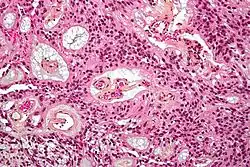

| Micrograph of an ependymoma. H&E stain. | |

Ependymomas are composed of cells with regular, round to oval nuclei. There is a variably dense fibrillary background. Tumor cells may form gland-like round or elongated structures that resemble the embryologic ependymal canal, with long, delicate processes extending into the lumen; more frequently present are perivascular pseudorosettes in which tumor cells are arranged around vessels with an intervening zone consisting of thin ependymal processes directed toward the wall of the vessel.[5]

-

Micrograph of a myxopapillary ependymoma. HPS stain. -